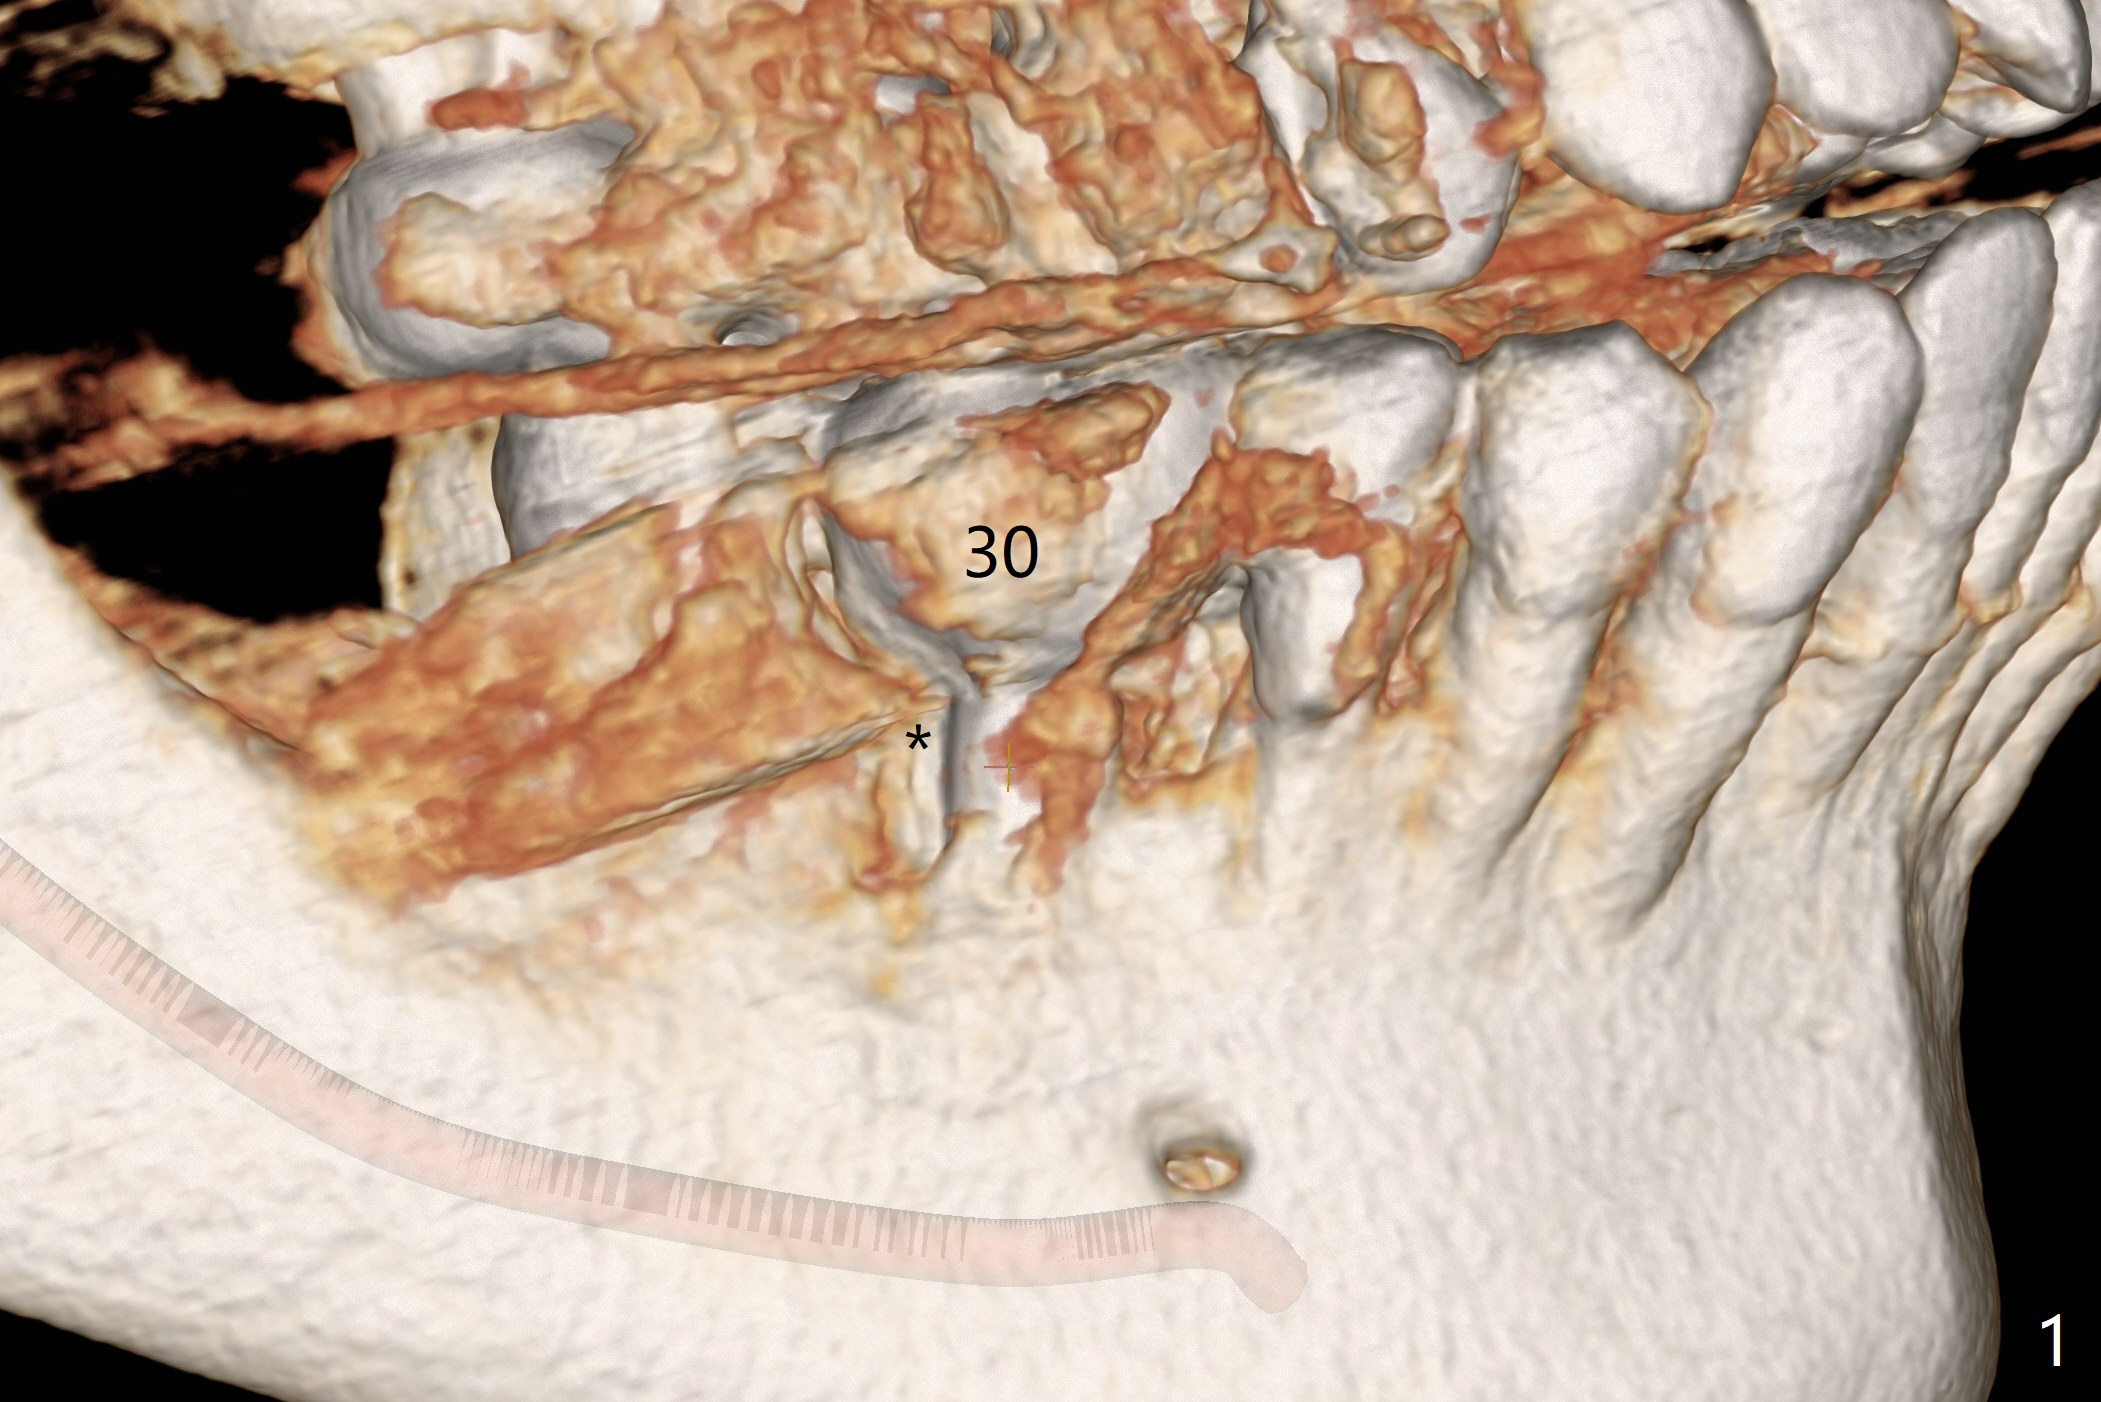

Twenty six months post cementation, periimplantitis develops buccally at #30 (Fig.1) due to buccal (B) placement (Fig.2) with buccal thread exposure (red line), as compared to the same sized implant at #19 (Fig.3). After removal of the crown and abutment and incision, use Titanium brush to clean the exposed threads. Following implant removal and removal of the lingual bone, place the same implant lingually (Fig.4 arrow) with the used-to-be-exposed surface facing lingual (Fig.4 red line). The buccal gap will be filled with autogenous bone harvested lingually and allograft. Use 2-3 pieces of PRF membranes to close the wound, i.e., to bury the implant. A 5x13 mm implant (Fig.5) placed lingually (Fig.6 L) appears to be unable to gain more than .77 mm native bone (Fig.7). Lab declines to make a guide.